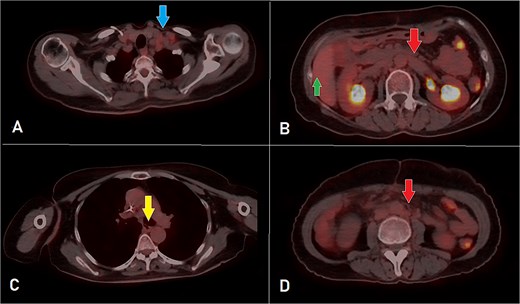

A computed tomography (CT) scan was performed, and the patient underwent a right hemicolectomy using a laparoscopic-assisted approach, with en bloc resection of the tumor and lymphadenectomy. The procedure was uneventful, with no intraoperative complications, and the patient had an unremarkable immediate postoperative recovery. The staging was determined as T4bN2bMx. Further imaging revealed enlarged mediastinal, supraclavicular, and retroperitoneal lymph nodes, with a solitary liver lesion (Fig. 1). A biopsy from the supraclavicular node indicated moderately differentiated adenocarcinoma of gastrointestinal origin. Molecular profiling showed wild-type RAS, intact MSI, mutant BRAF, and HER2 negative. The patient was started on capecitabine-oxaliplatin (CapeOX) with bevacizumab and completed 11 cycles with a marked clinical and radiological response (Fig. 2).

PET-CT scan at the corresponding cuts to Fig. 1 showing great metabolic and morphological regression regarding the previously seen (A) supraclavicular lymph nodes (arrow); (B) retroperitoneal lymph nodes (inferiorly pointing arrow) and hepatic lesion (superiorly pointing arrow); (C) mediastinal (para-oesophageal – station VIII) lymph node (arrow); and (D) retroperitoneal lymph nodes (arrow).